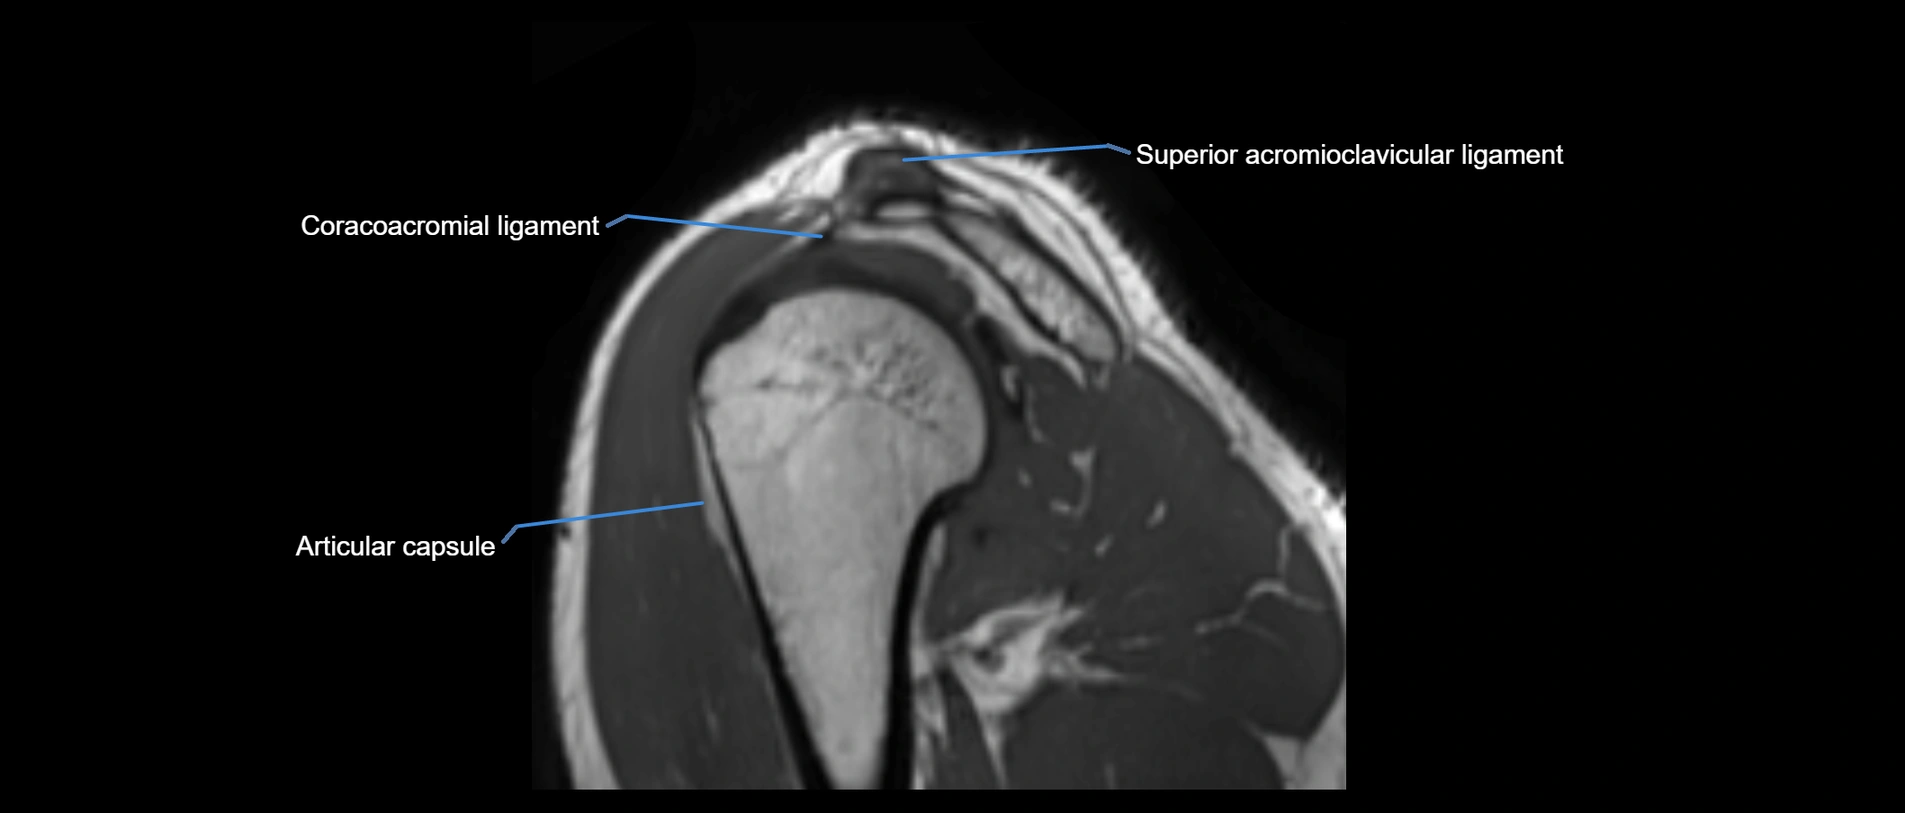

MRI Appearance

• T1-weighted images:

• Normal ligament: Low signal (dark linear band) spanning acromion to clavicle.

• Surrounding fat planes: Bright, delineating the ligament clearly.

• Marrow of clavicle and acromion: Bright due to fatty content.

• Tears: Discontinuity or irregular thickening with intermediate-to-bright signal.

• Chronic injury: Thinning, fraying, or irregular low-signal fibers with adjacent scarring.

• T2-weighted images:

• Normal ligament: Low signal, homogeneous.

• Partial tear or sprain: Focal hyperintensity or thickening.

• Complete tear: Discontinuity with fluid-bright gap between clavicle and acromion.

• Associated edema: Bright signal in distal clavicle or acromion marrow.

MRI images

image